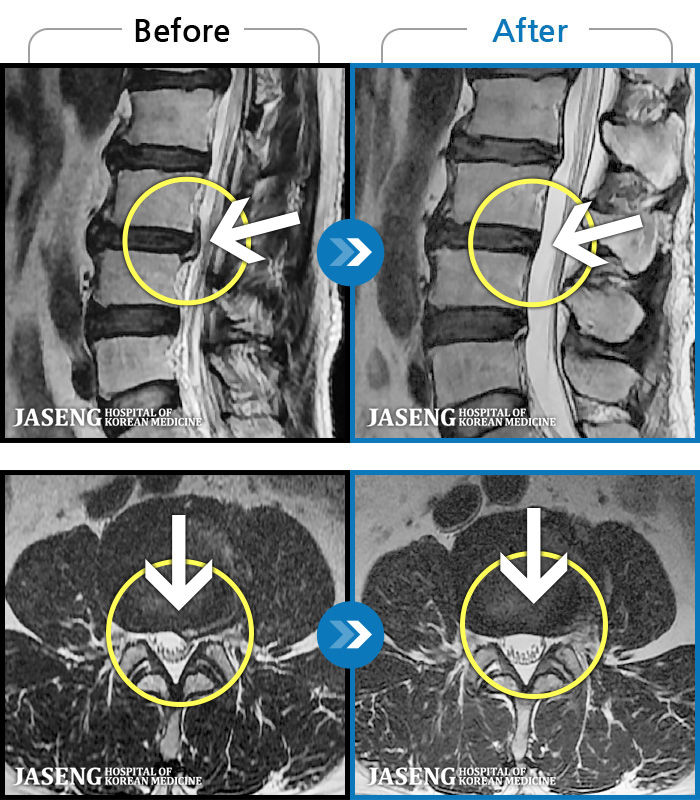

MRI로 보는 치료결과

1,228건의 MRI 전후 사진으로 터진 디스크 흡수 사례를 확인하세요.

[해운대] 23.09.18~25.01.27

※ 환자분에게 사전 동의를 받아 동일 조건에서 촬영되었으며, 개인에 따라 치료 후 부작용이 발생할 수도 있으니 사전에 의료진과 상담 후 치료를 진행하시기 바랍니다.